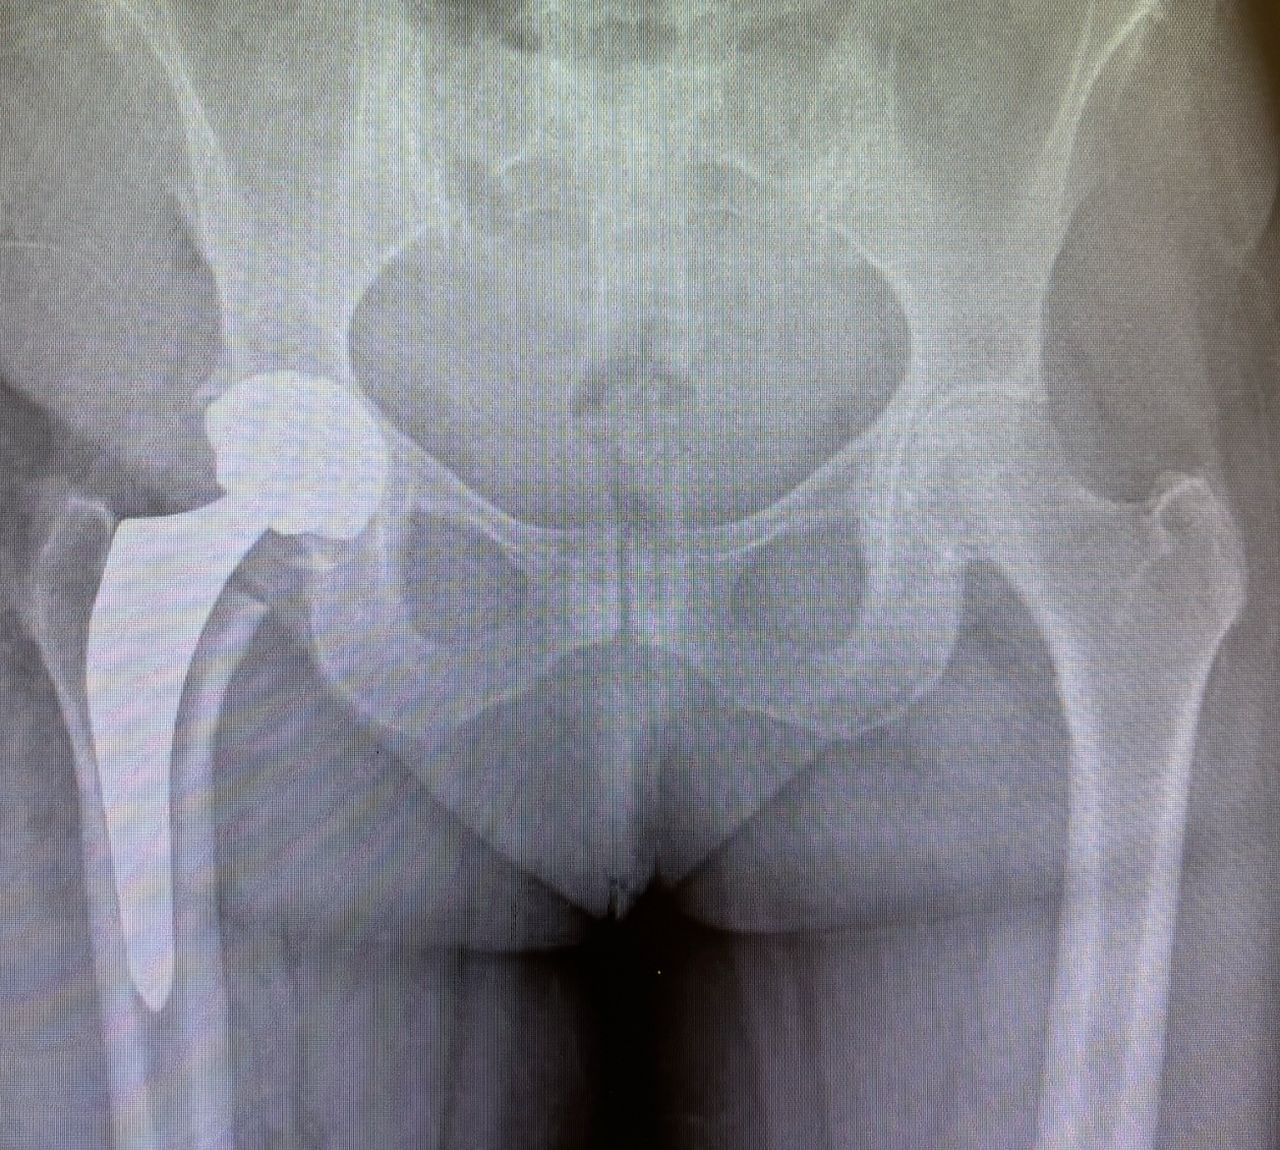

Ho maturato una solida esperienza nella chirurgia protesica mini-invasiva di anca e ginocchio. Eseguo interventi di protesi di anca mediante accesso anteriore “bikini” e accesso posterolaterale, interventi di protesi di ginocchio sia monocompartimentale che totale. Tratto la traumatologia sportiva di ginocchio e spalla mediante l’utilizzo di tecniche artroscopiche mini-invasive.